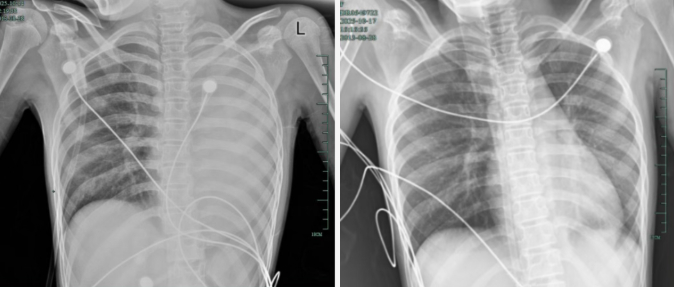

入院后,玲玲很快出现呼吸急促、胸闷胸痛症状,体温38.5℃,只能靠 5L/min 的面罩吸氧维持血氧,胸片显示左肺已完全呈 “白肺” 改变,肺部炎症进展迅猛

治疗前,左肺呈“白肺”状态;治疗后,“白肺”被吸收,心脏边缘清晰可见。